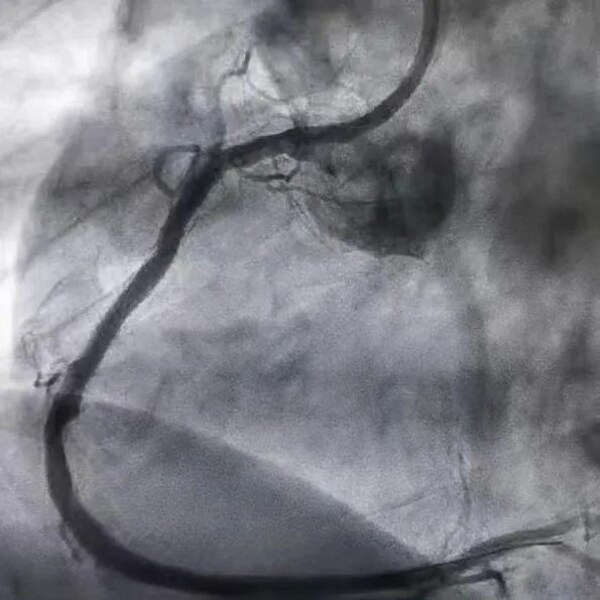

近日,上海德达医院葛均波院士团队抢救了一位新冠病毒感染7天,支架内血栓导致急性心梗的患者。经过急诊手术,从堵塞的右冠抽出巨大血栓,心脏动脉血流恢复正常,患者转危为安。